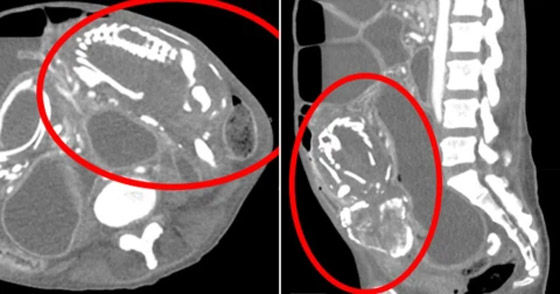

توفيت امرأة إفريقية تبلغ من العمر 50 عاما في نيويورك، بحالة نادرة بسبب وجود جنين متحجر في بطنها لمدة 9 سنوات. وزارت المرأة الأطباء في نيويورك تشكو من تقلصات في المعدة وعسر هضم وصوت غرغرة بعد تناولها للطعام. كشفت الفحوصات وجود جنين متحجر في بطنها، ضغط على أمعائها لفترة طويلة ومنعها من امتصاص الغذاء بشكل جيد ما أدى إلى وفاتها نتيجة نقص التغذية الحاد.

الظاهرة النادرة، التي تم تسجيلها حوالي 300 مرة فقط، تحدث عندما يموت الجنين الذي ينمو خارج الرحم أثناء الحمل ولا يتم إخراجه من الجسم. وقد توفيت المرأة بعد 14 شهرا من وصولها إلى الولايات المتحدة، وقال الأطباء إنها ماتت نتيجة سوء التغذية الحاد.